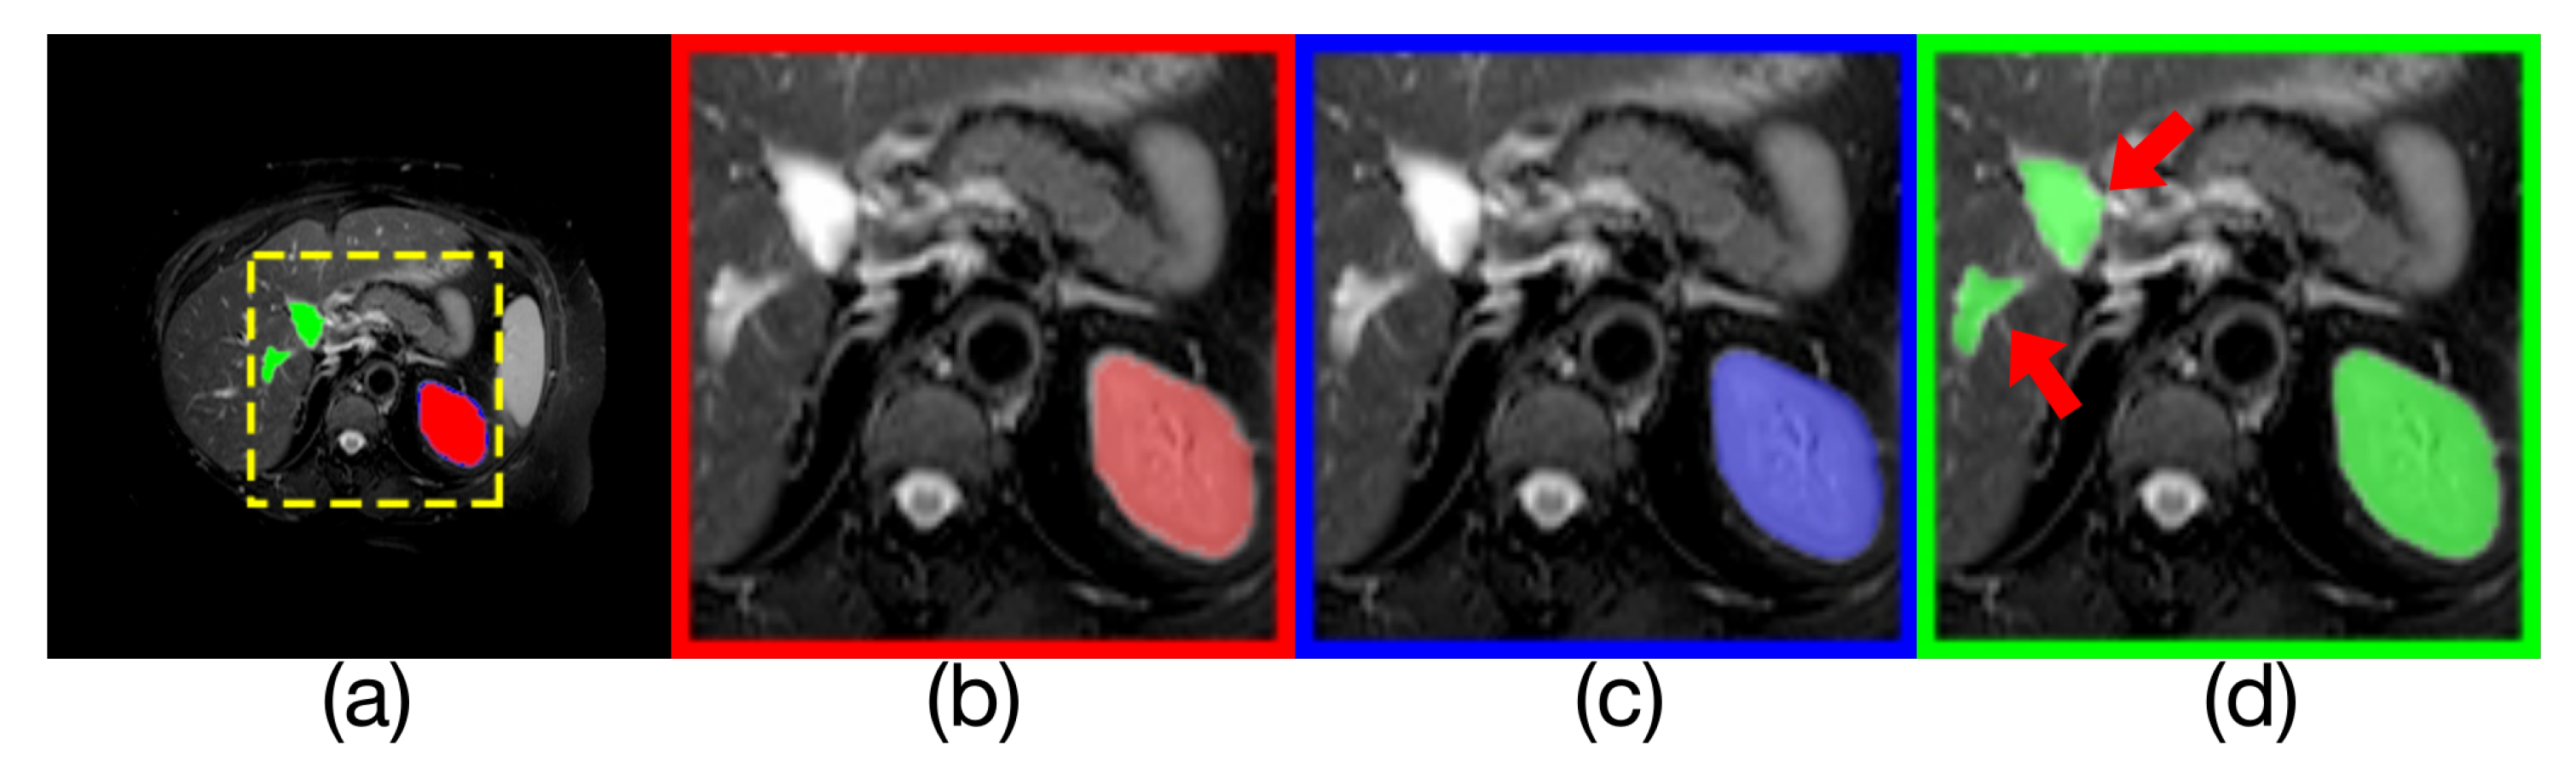

Table 2 compares the liver segmentation performance on CT images, where Render U-Net had the best performance. The output of model and the manually annotated result are compared in Figure 9. Our proposed network increased IoU by over 0.0484 [24], and increased the Dice coefficient by 0.0253, increased precision by 2.1 percentage points, and increased the recall rate by 2.96 percentage points.

Figure 9. Comparison of model outputs and ground truth. (a) shows the other three figures stacked from top to bottom, where the predicted extra areas are clearly seen. The red area in (b) is the manually annotated result. The blue region in (c) is the output of Render U-Net. The green region in (d) is the output of Attention U-Net. Some areas with incorrect predictions are indicated with red arrows in the figure.